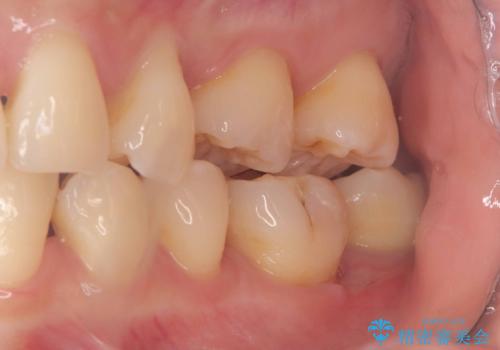

- 銀歯の下に虫歯が見つかりました。一度治療されている歯であり、レントゲン上では虫歯が神経に近い位置まで進行している様子が確認されました。

ただし、自発痛の既往はなく、歯髄診の結果も正常であったため、虫歯除去中に露髄した場合には生活歯髄療法(VPT)を行う方針としました。

実際の治療ではVPTを施行し、その後痛みなどの症状もなく経過は良好でしたので、最終的にセラミックインレーによる修復を行いました。